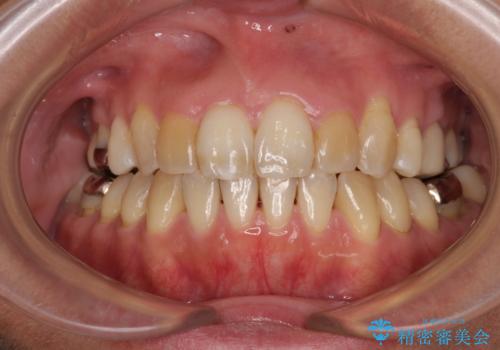

[ インビザライン ] 前歯のガタつきをマウスピース矯正で改善